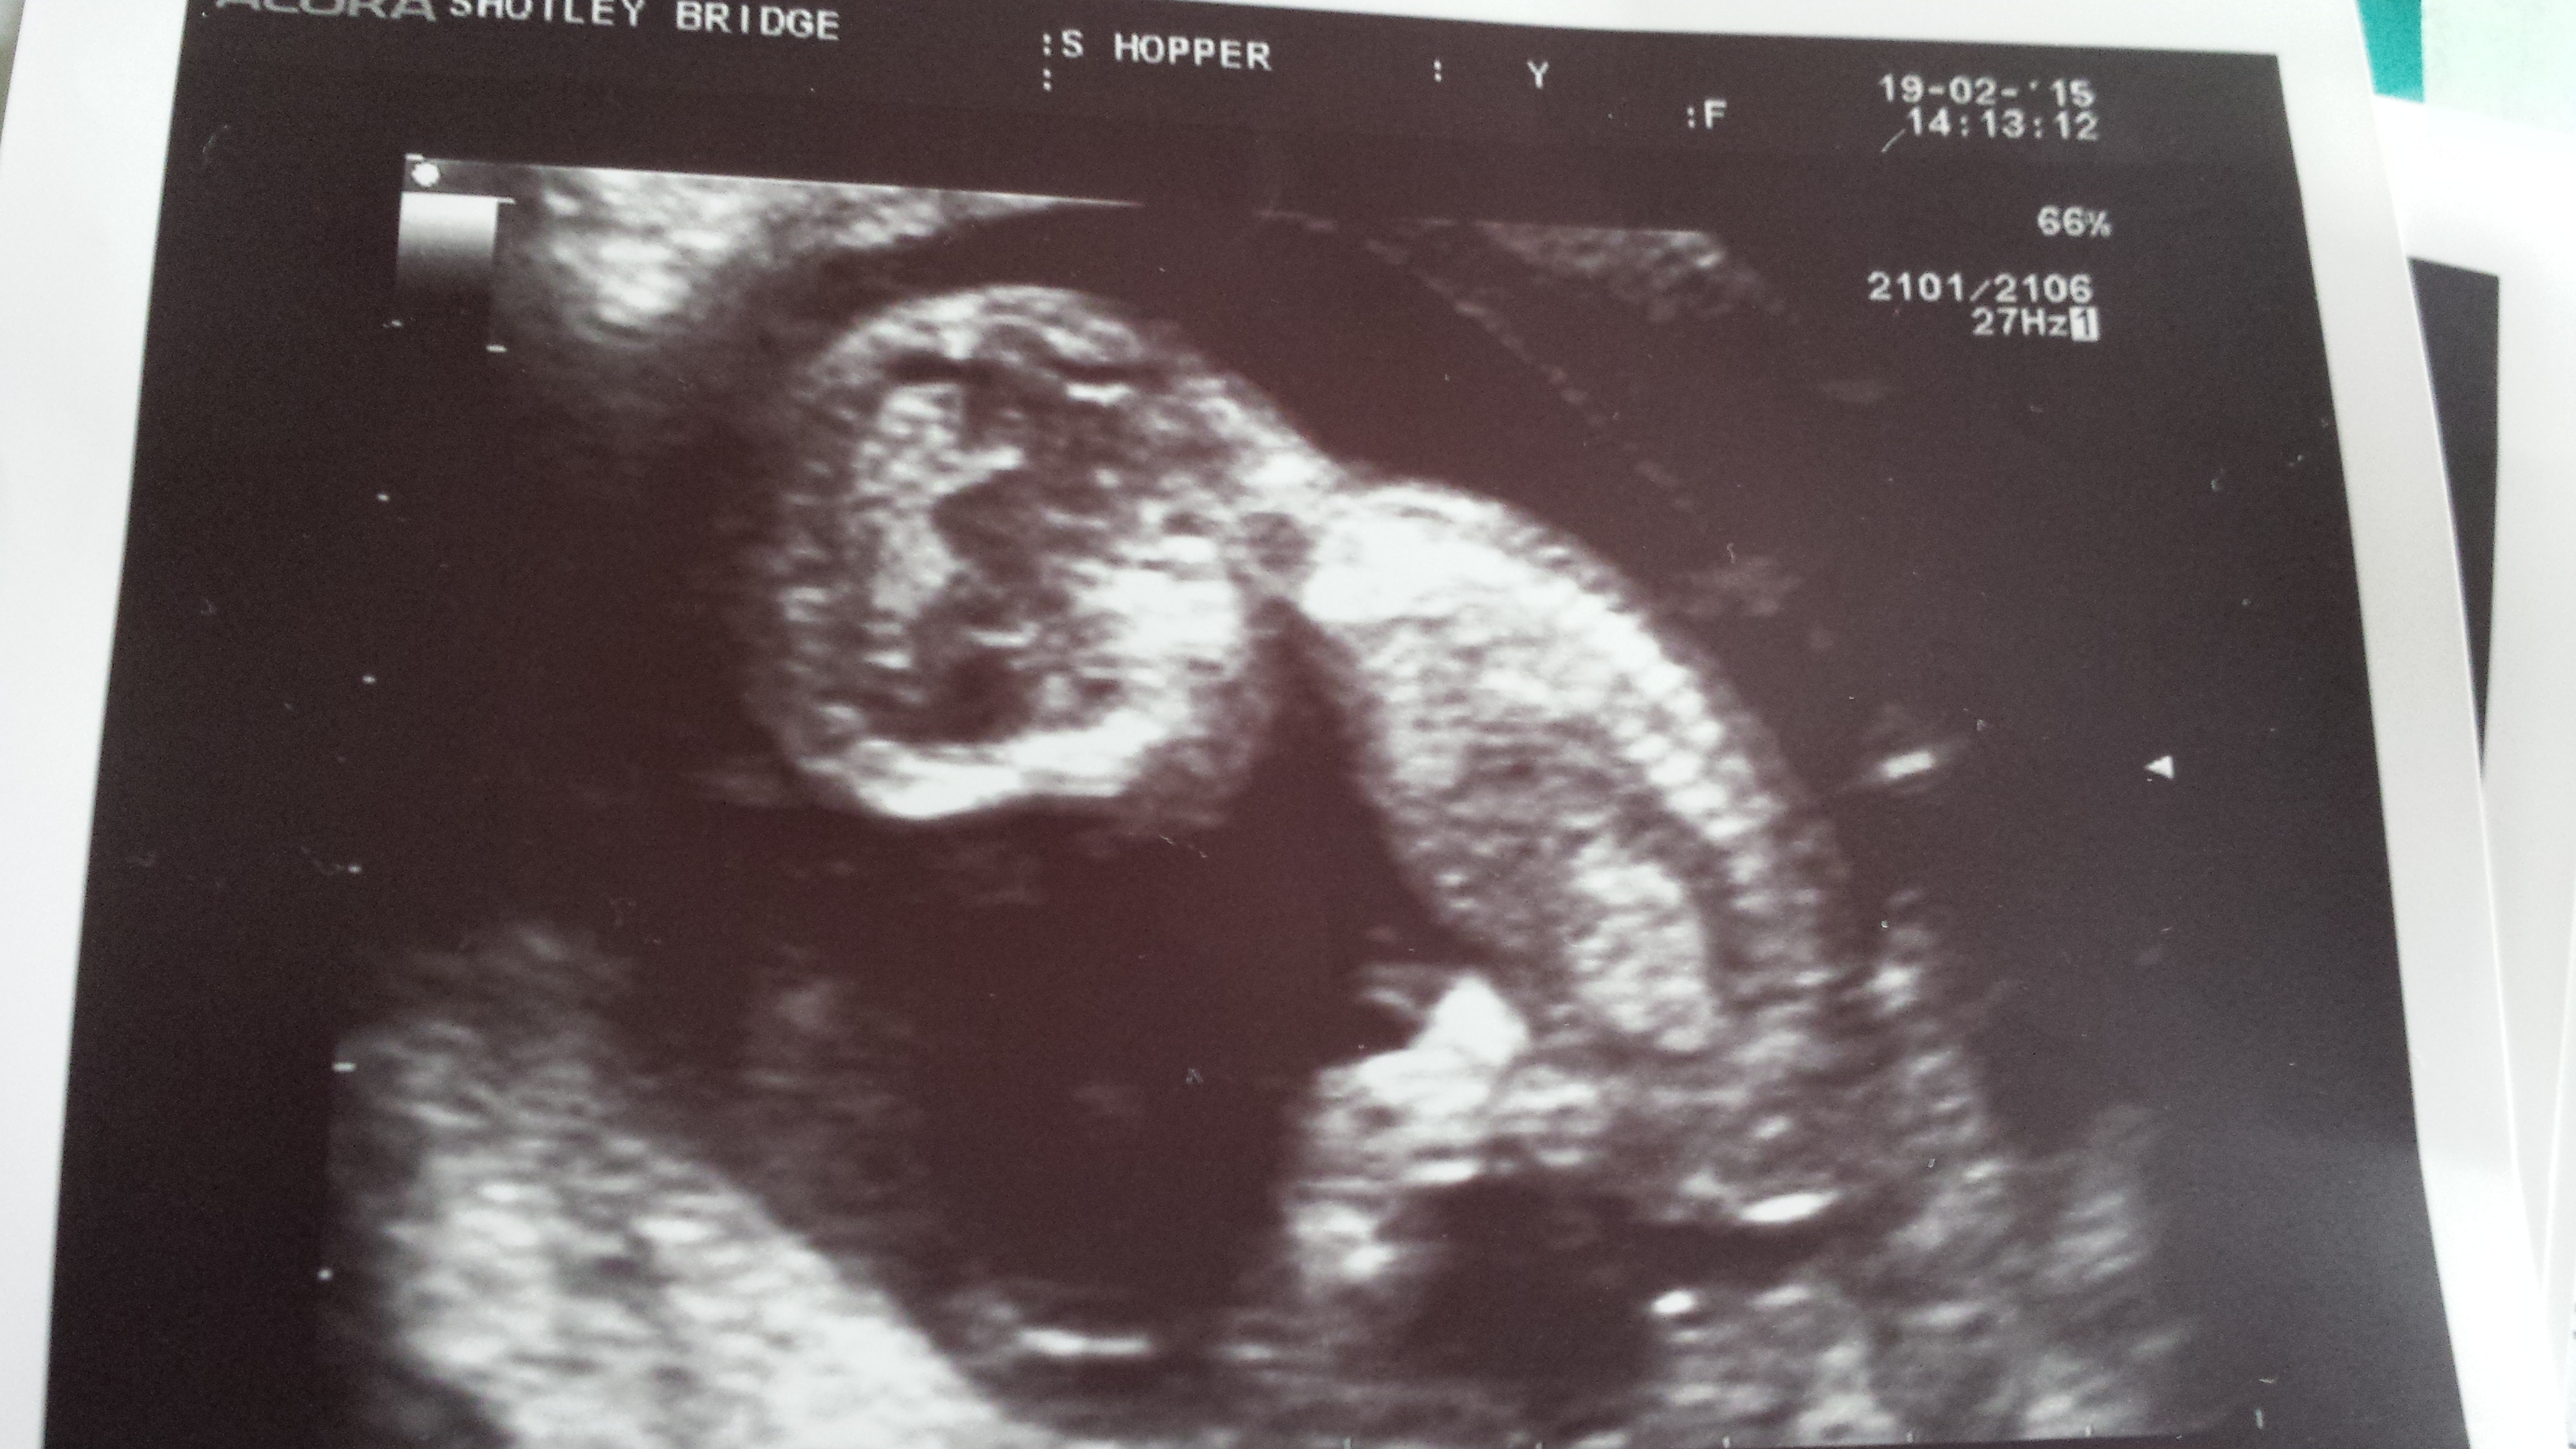

99% sure there is not one clue on gender between the 3 pics. Wanted to double check with you lovely ladies. Find out in just over 2 weeks. TIA.

I don't see any gender clues but get a boy vibe.

From my understanding of skull theory i'd say boy.

The baby is back out so no gender clues but from skull I'd say boy